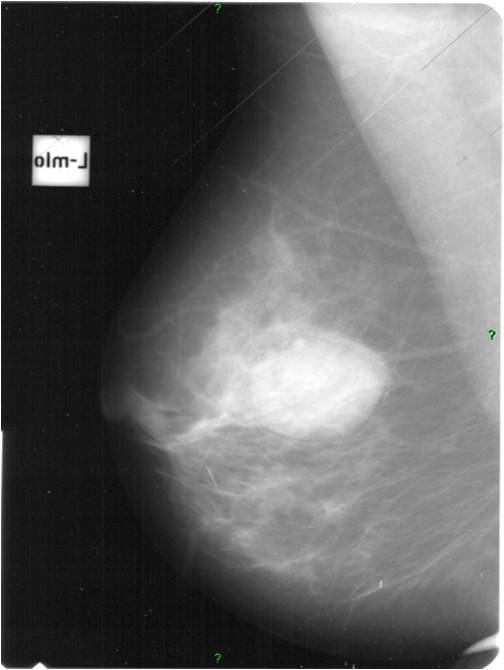

2. Digital mammography has displaced the analogue technic for today almost everywhere: (pictures 1,2,3) phosphorous plate or direct digital methods. For breast imaging the latter is the method of choice. Phases of image production separate. The image is produced on the detectors, but appears on the high resolution monitor and can be stored as a digital data set at various storage mediums (e.g.: CD, hard disk drives).

Image

Picture 2.

Picture 3.